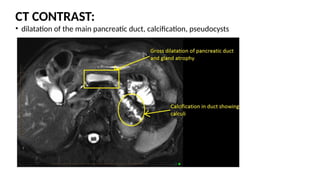

CT CONTRAST:

โ€ข dilatation of the main pancreatic duct, calcification, pseudocysts